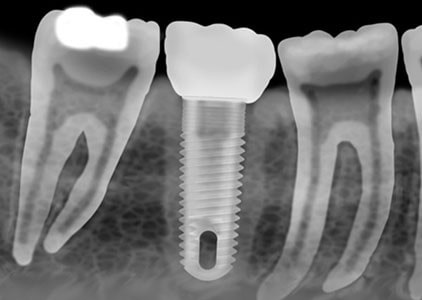

جراحی کاشت دندان فرآیندی است که در آن ریشه دندان با پست های / پایه های پیچ مانند فلزی جایگزین شده و به جای دندان آسیب دیده یا افتاده جایگزین می شود و عملکرد آن بسیار شبیه دندان اصلی است. جراحی کاشت دندان می تواند جایگزین مناسبی برای دندان های مصنوعی یا بریج هایی باشد که به خوبی در جای خود قرار نمی گیرند و می تواند در هنگام نبود ریشه طبیعی دندان به دندان مصنوعی یا بریج امکان جایگزینی دهد.

قرار دادن ایمپلنت دندان

در طی جراحی به منظور قرار دادن کاشت دندان، جراح دهان و دندان یک برش برای باز کردن لثه و رسیدن به استخوان ایجاد می کند. در درون استخوان حفره هایی ایجاد می شود تا پست (پایه) ایمپلنت در آن قرار گیرد. از آنجایی که پایه نقش ریشه دندان را بازی می کند، باید در عمق استخوان قرار بگیرد.

صبر کردن برای رشد استخوان

زمانی که پایه فلزی ایمپلنت در استخوان فک قرار گرفت، ادغام استخوان و ایمپلنت آغاز می شود. در طی این فرآیند، استخوان فک رشد می کند و با سطح ایمپلنت دندانی ترکیب می شود. این فرآیند که می تواند چندین ماه زمان برد، به ایجاد پایه محکم برای دندان مصنوعی جدید کمک کرده و همانند ریشه های دندان اصلی عمل می کند.